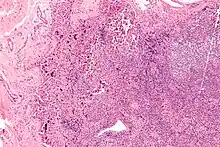

Lymphadenopathy due to systemic lupus erythematosus with characteristic necrosis and haematoxylin bodies. H&E stain.